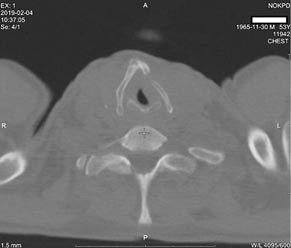

В феврале 2019 г. при повторной мультиспиральной компьютерной томографии было установлено, что компьютерно-томографические признаки в динамике больше соответствуют фиброзно-кавернозному туберкулёзу в верхних долях обоих лёгких и 6-м сегменте справа, в фазе инфильтрации и распада (рис. 2). Обнаружено патологическое образование гортани с деструктивными изменениями щитовидного хряща (рис. 3).

Рис. 3. Мультиспиральная компьютерная томография, снимок пациента от 04.02.2019: деформация и фрагментация щитовидного хряща